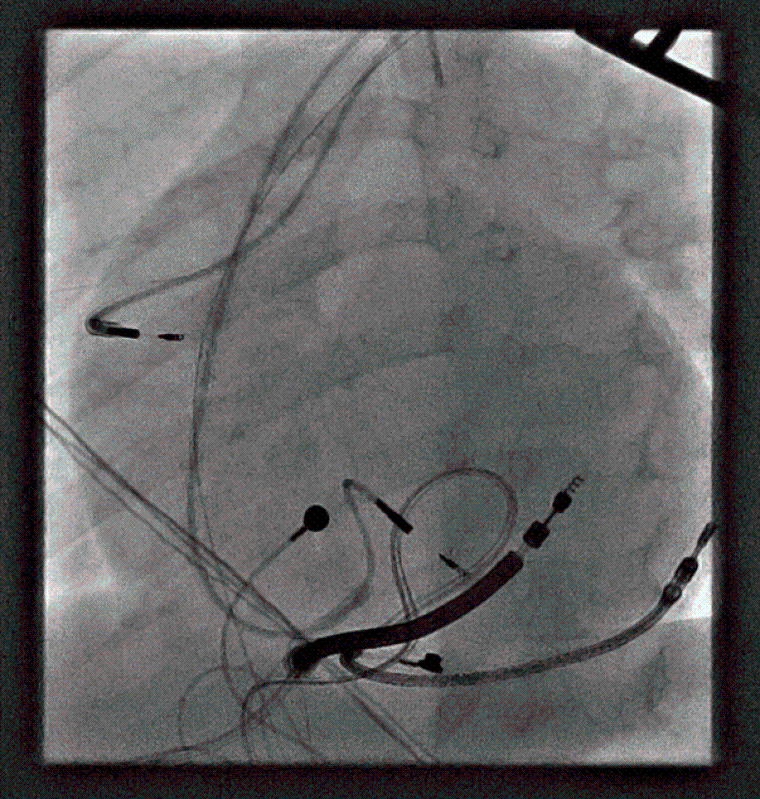

Amongst others, CaM is tethered to the pre-IQ motif of L-type calcium channels (ICaL) (Image 1) and to the slow component of the delayed-rectifier potassium channels (IKs), modulating their function by either stimulating or inhibiting them. Variants in CaM cause a gain of function of these inward current channels, resulting in prolongation of the QTc8,9.